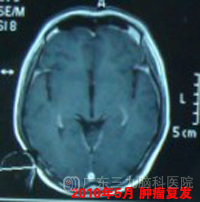

2008年8月底,崔先生转入广东三九脑科医院治疗,在接受了脑室腹腔分流术后,于9月开始在广东三九脑科医院肿瘤综合治疗中心接受治疗,予以全脊髓放疗,颅内肿瘤60Gy,脊髓44Gy。2008年9月-09年2月行6疗程低毒性化疗,放化疗后复查MR示肿瘤明显缩小。2009年5月复查头颅MR示松果体区结节影较前稍增大,针对该病灶行X刀治疗。www.999brain.com

此后崔先生定期复查,期间见肿瘤逐步缩小,2010年5月复查头颅MR示原松果体区未见肿瘤复发,双侧颞叶,右侧额叶及胼胝体互补偏右多发异常信号影,2010年5月至10月再行3程化疗。此后复查复发部位病灶逐步缩小,未见其他部位新发病灶,目前已复发治疗后随访两年余,患者情况良好,颅内情况稳定,建议可1年后复查。www.999brain.com